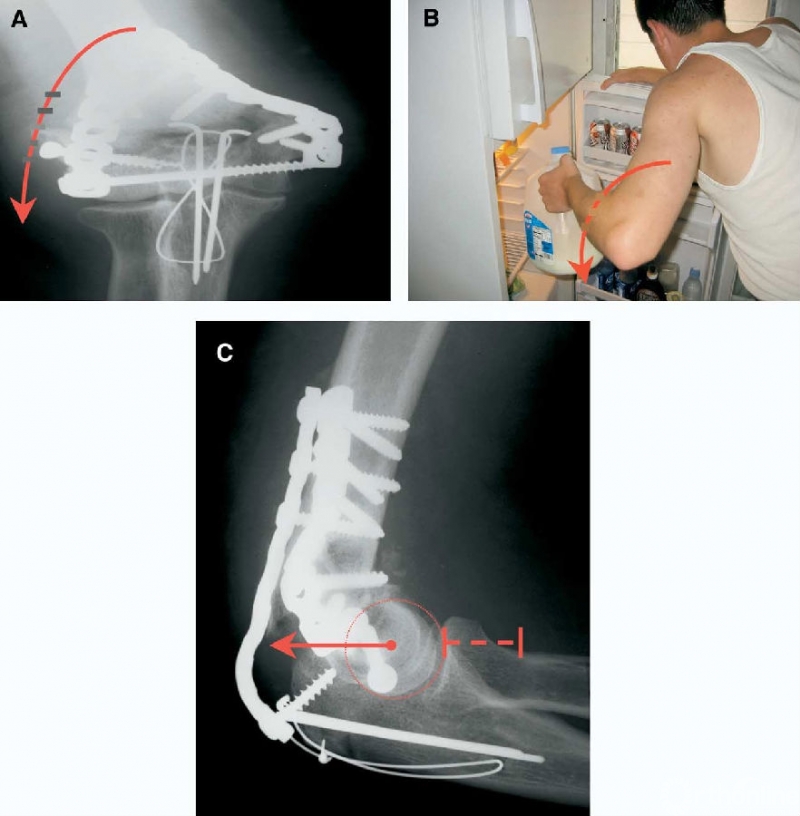

图10 基于上述原理的肱骨远端粉碎性骨折固定技术影像学实例。通过使用这种方法,内固定足以支撑患者进行早期主动和被动康复功能锻炼,而不用担心内固定失效。

图11 外侧柱失效(内翻)。A:内固定失效通常发生于外侧柱,由于反复的重力和肘关节内翻应力导致。将肘关节正位X线片转至水平位,可以更容易理解施加内翻应力的机制。B:通过将外侧柱钢板放置在侧方的矢状面上,使螺钉在这个方向向内穿过内侧面,可以最大程度减小这种内固定失效机制。C:当肘关节屈曲90°时,内翻应力将外侧柱和肱骨小头从外侧柱后方的钢板上拉开。螺钉失效是由于其被直接从粉碎的骨块中拔出。